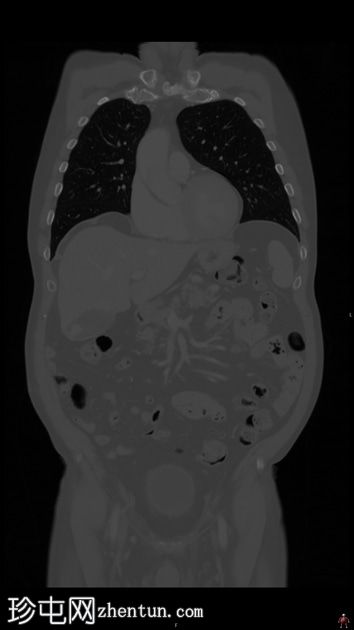

MRI

轴位

T2加权像

行MRI检查以明确病因。 MRI显示胆囊底部有一孤立性息肉样病变,突入胆囊内,大小约为21 mm x 17 mm。病变表面可见高T1信号,可能代表血液成分。病变早期增强扫描后强化程度较正常胆囊壁更为明显。